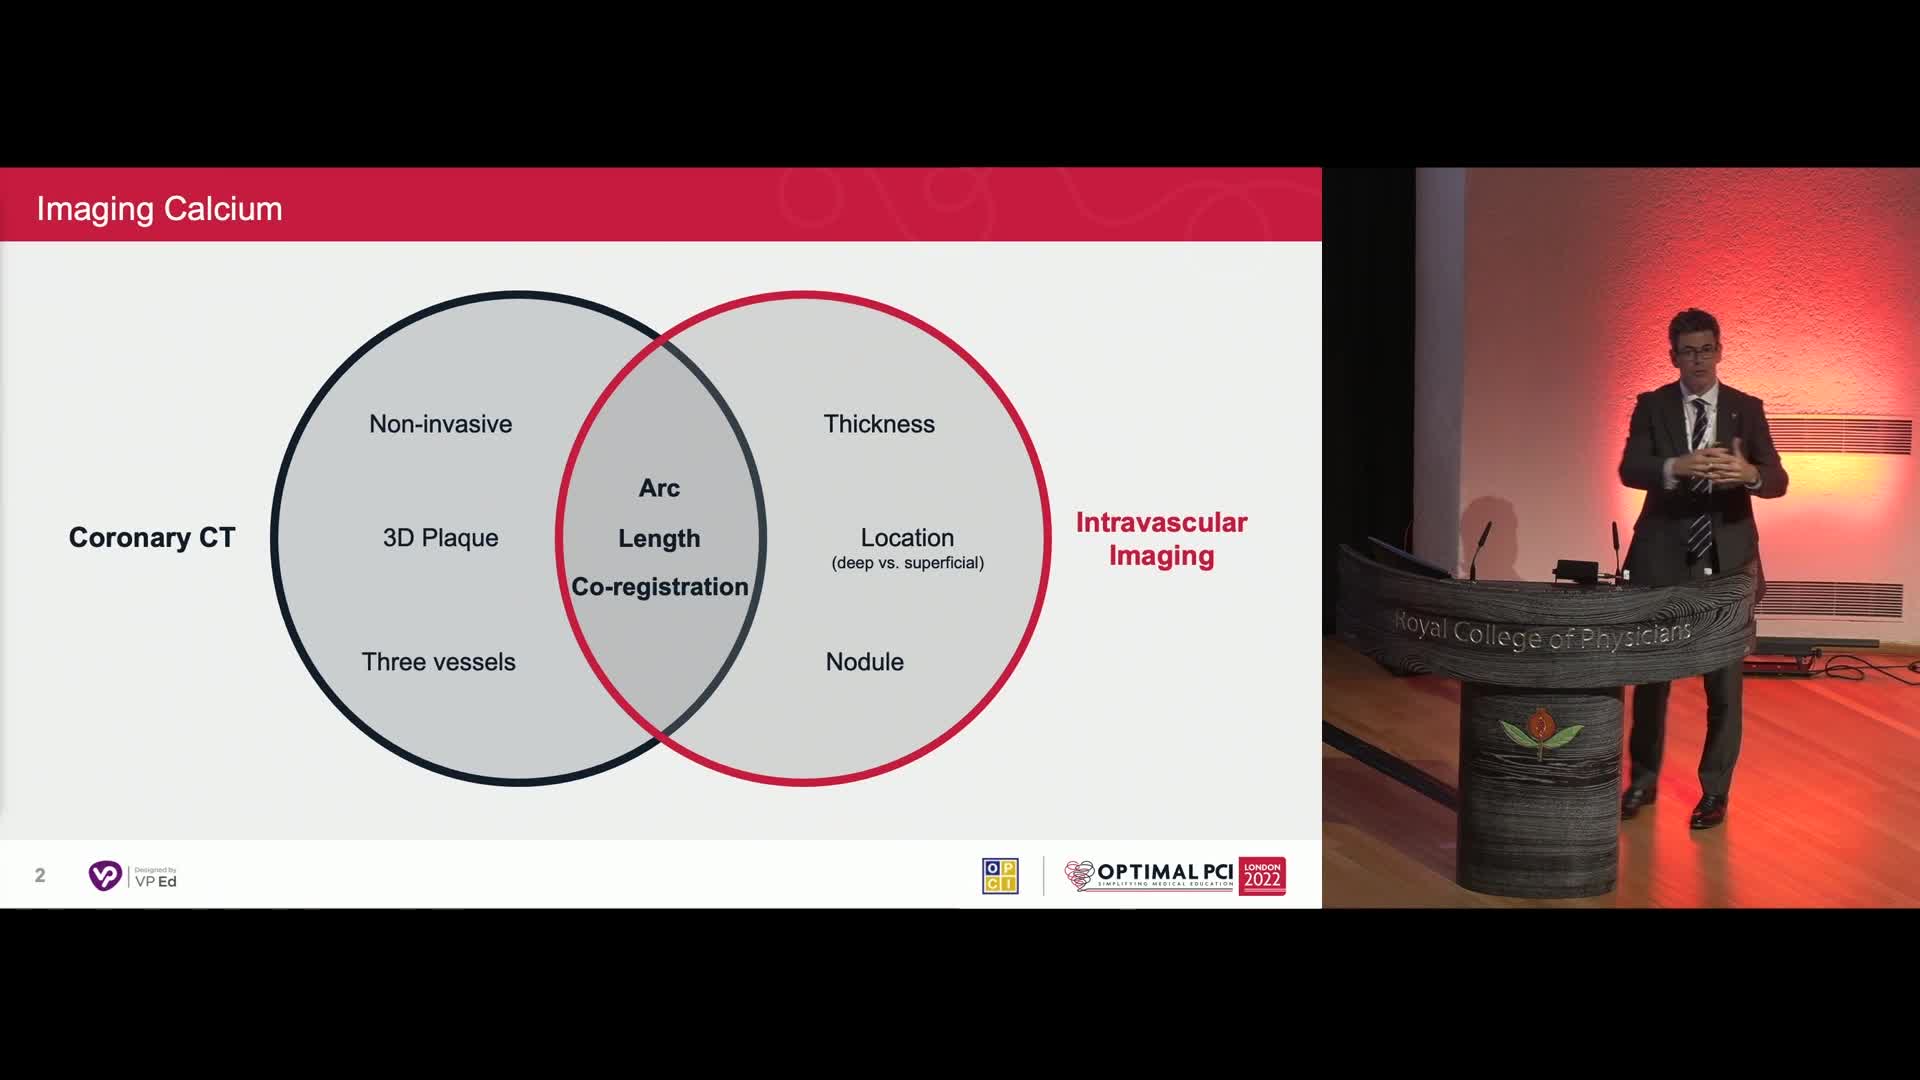

Session 2: Coronary calcium – too hard to crack?

Treatment of coronary arterial calcium (CAC) has being redefined. We explore the interaction between CAC and patient...